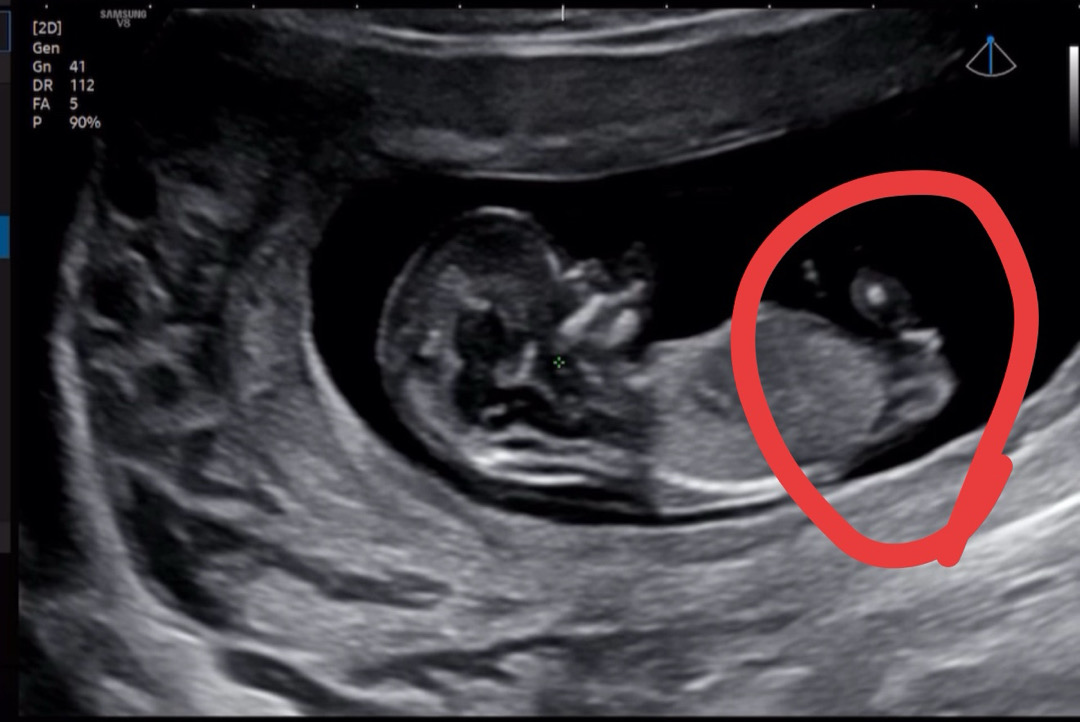

12주 1일차

각도법 봐주세요